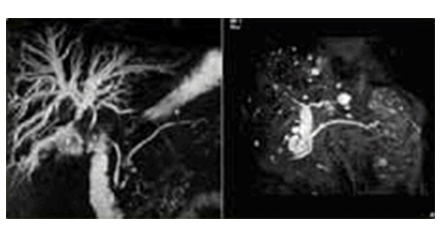

• 췌담도 자기공명 영상(MRCP) 이미지

췌담도 자기공명 영상

(MRCP)

T2효과가 매우 강조된 영상 기법을 이용하여 췌관액이나 담즙의 고신호강도와 주변 조직간의 신호 차이를 최적화 시킴으로써 담도와 췌관을 영상화 합니다. 특히 담도가 폐쇄된 부위의 상부 담도 조영을 검사 하는데 있어 매우 탁월한 정보를 제공합니다.